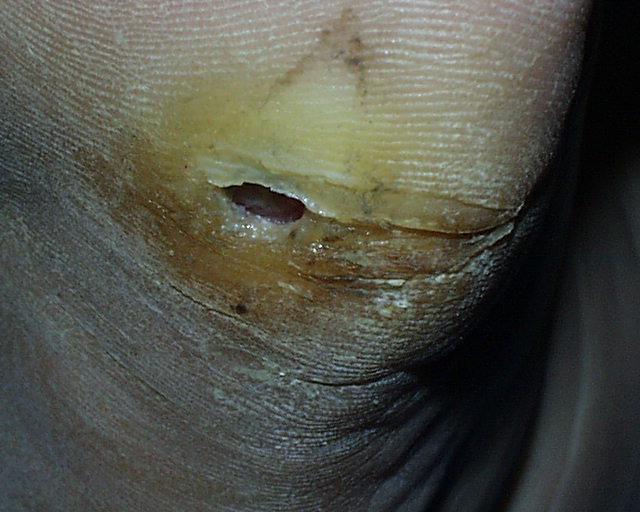

In terms of the infecting microorganisms and the likelihood of successful treatment with antimicrobial therapy, acute osteomyelitis in people with diabetes is essentially the same as in those without diabetes. Chronic osteomyelitis in patients with diabetes mellitus is the most difficult infection to cure. Adequate surgical debridement, in addition to antimicrobial therapy, is necessary to cure chronic osteomyelitis.

In chronic osteomyelitis, a sequestrum and involucrum form; these represent islands of infected bone. Bone fragments that are isolated have no blood supply. Administered antibiotics do not penetrate the devascularized infected bone fragments; they can enter the area of osteomyelitis only via the remaining blood supply. Therefore, antibiotic therapy alone cannot cure patients with chronic osteomyelitis without surgical debridement to remove these isolated infected elements. Surgical debridement is essential to remove the infected bony fragments that the antibiotics cannot reach so that affected areas can be treated with antimicrobial therapy.

Chronic osteomyelitis cannot be cured without adequate surgical debridement.

Appropriate consultation with a surgeon should be obtained for debridement and/or amputation in chronic osteomyelitis.